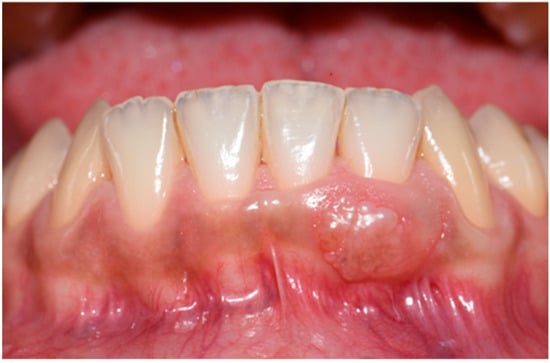

2. Case Report